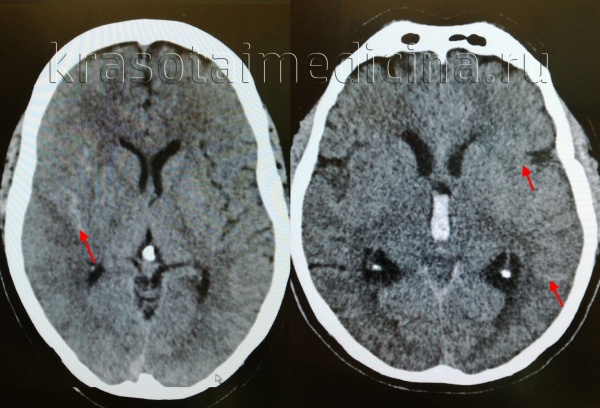

(а) КТ, аксиальный срез: в бороздах, левой сильвиевой щели, обводной цистерне, а также в межполушарной борозде определяется гиперденсное субарахноидальное кровоизлияние.

(б) Бесконтрастная КТ, аксиальный срез: небольшое скопление гиперденсной жидкости вдоль левой средней лобной борозды, представляющей собой травматическое субарахноидальное кровоизлияние.